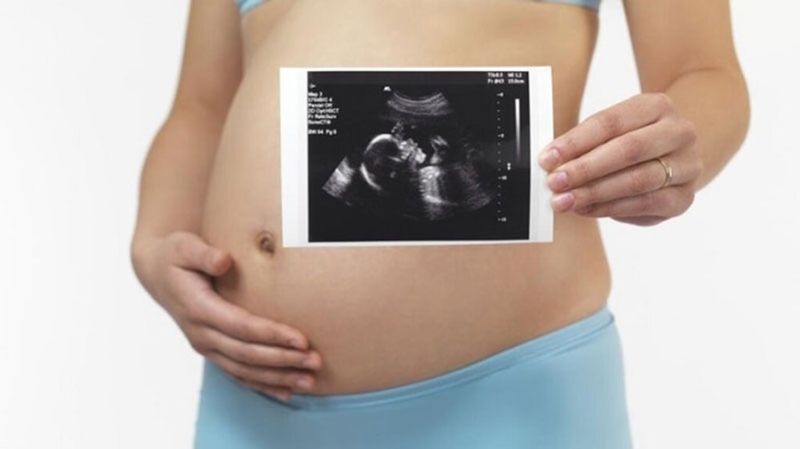

Nỗi bâng khuâng của các mẹ bỉm khi mang thai là nên siêu âm tim thai ở tuần thứ mấy? Theo như các chuyên gia khoảng thời gian thích hợp nhất đối với thai kỳ sức khỏe của mẹ bình thường là tuần 18-22. Tuy nhiên, cũng có thể siêu âm tim thai sớm hơn 1-2 tuần cũng tốt.

Được biết đây là khoảng thời gian thích hợp nhất và cực kỳ quan trọng được các mẹ chào đón trong quá trình kiểm tra dị tật của thai nhi trong bụng. Dựa vào kết quả kiểm tra từ đó các mẹ sẽ được hướng dẫn cách chăm sóc thai nhi thích hợp hơn.

Cột mốc quan trọng trước khi siêu âm tim thai rơi vào tuần thứ 12 và 22, trong tuần này, mẹ bầu không chỉ được siêu âm mà còn cần thực hiện nhiều xét nghiệm sàng lọc cơ bản. Khi khám thai tuần thứ 12, mẹ bầu sẽ được chỉ định xét nghiệm máu, xét nghiệm nước tiểu, làm double test và các thăm khám khác.